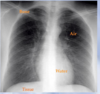

What is the red arrow indicating?

Is this a normal finding on a CXR?

A

• Gastric bubble

• This is a normal finding on a CXR

Free air: Instead of the air being contained inside the stomach to the unitlateral side of the diaphgram, air will be displaced bilaterally on both sides of the diaphragm.